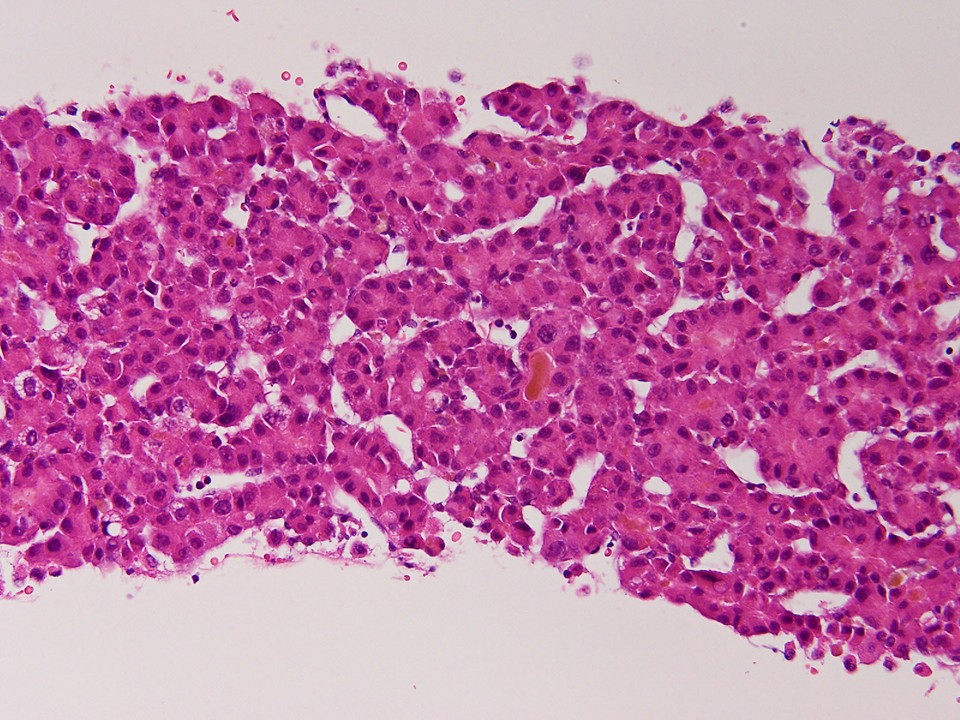

組織所見

索状に増殖する肝細胞癌で、褐色色素は胆汁であった。核内偽封入体も観察された。